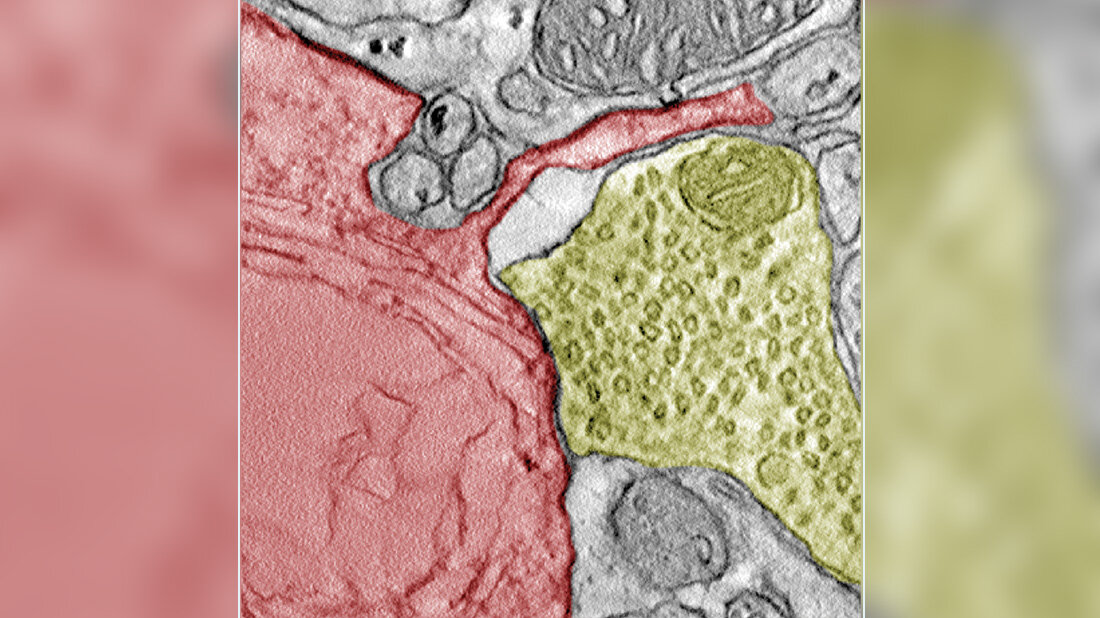

Für ihre Forschung analysierten die Forschenden Daten, durch die sie eine Reihe von Genen identifizierten, die mit der Synapsenbildung in Verbindung stehen. In Zellkulturen und im Mausmodell bestätigte sich die Entdeckung, dass Zellen des kleinzelligen Lungenkrebs funktionale Synapsen mit Neuronen bilden. „Ich war verblüfft, als wir das Ausmaß der Neuronen sahen, die die Krebszellen kapern konnten”, erklärt Seniorautor Professor Dr. Matteo Bergami, Forschungsgruppenleiter am Exzellenzcluster für Alternsforschung CECAD der Universität zu Köln. „Ich glaube, dieses Ergebnis wird die Medikamentenentwicklung transformieren und zu effizienteren Therapien führen, die eine Metastasierung des kleinzelligen Lungenkrebses im Gehirn verhindern.“

Als verantwortliche Neurotransmitter konnten die Forschungsgruppe Glutamat und GABA ausfindig machen. Waren sensorische oder kortikale Neuronen involviert, konnte der Krebs schneller wachsen. Die Zellen zeigten eine hohe Anpassungsfähigkeit zur Beschleunigung des eigenen Wachstums. Die Hemmung von Glutamat führte zur verringerten Tumorlast und die Mäuse konnten länger Überleben – es könnte sich daher als neuer Angriffspunkt für weitere Therapieansätze entpuppen. Diese Form der Therapie ließe sich auch mit einer Chemotherapie kombinieren.